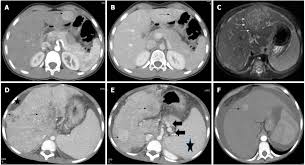

Signs and symptoms of pediatric liver cancer. These symptoms may be caused by liver cancer or other health problems. Called ascites, the fluid builds because the. Excess alcohol, hepatitis, and diabetes are risk factors. Pain, especially at the top right of the abdominal area, near the right shoulder blade, or in the back. In addition, we conducted statistics for laboratory tests and found no obvious injury to liver function and kidney function (see table 3). Instead they are named by their site of origin, such as lung cancer metastatic to the liver. He also had hepatitis c and early stages of cirrhosis. Malignant tumors of the liver are most commonly metastases, or areas of distant spread, from tumors that arise elsewhere in the body. Treatment depends mainly on where the cancer also, you may have diarrhea and a feeling of fullness in the abdomen. Liver cancer may not cause any signs or symptoms in its early stages. 2 frederick national laboratory for cancer research conclusions: .signs of pancreatic cancer (changes in the pancreas reveled by the ultrasound and abdominal ct;

If you have any of these symptoms, you should tell your doctor so that problems can be diagnosed and treated as early as. Liver cancer presents a special challenge because you may not notice any symptoms when the disease is starting and in its early stages. Liver cancer may not cause any signs or symptoms in its early stages. Malignant tumors of the liver are most commonly metastases, or areas of distant spread, from tumors that arise elsewhere in the body. Liver cancer occurs when the liver cells are out of control and the divide and multiply abnormally. They are produced in the body: Unfortunately, every complaint or symptom of cancer can be some cancers occur more frequently in certain age groups. According to the mayo clinic, liver disease can be caused by everything from alcohol use to obesity, and one common warning sign is something you probably wouldn't expect: Pain in the upper abdomen on the right side or near the right shoulder blade. Some cancers develop outside the liver and spread to the organ, but doctors only describe cancer that starts in the liver as liver cancer. Pneumococcal meningitis occurs in patients with diabetes mellitus, alcoholism, liver cirrhosis. Swelling in your legs and ankles. Signs and symptoms of pediatric liver cancer.